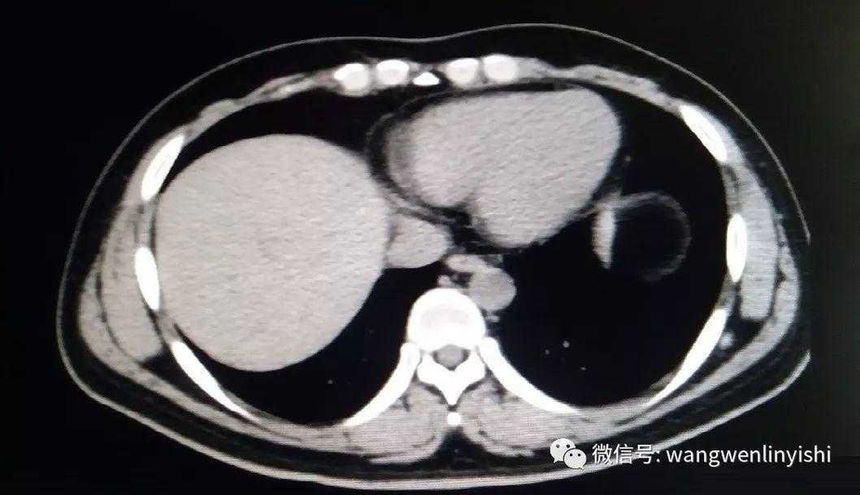

The upper part of the patient’s chest wall is protruded as a whole, coupled with depressions in the central and lower regions, presenting a classic example of Wenlin chest.

Wenlin chest is a distinctive chest wall deformity that was often mistakenly identified as pectus carinatum in the past. However, unlike PC, which is characterized by a single protrusion, Wenlin chest involves both protrusions and depressions, classifying it as a kind of complex chest wall deformities. This malformation can not be corrected by traditional surgeries that work for PC. Notably, the depression in Wenlin chest is only apparent in comparison to the protrusion of the upper chest wall, without significantly compressing the patient’s heart.